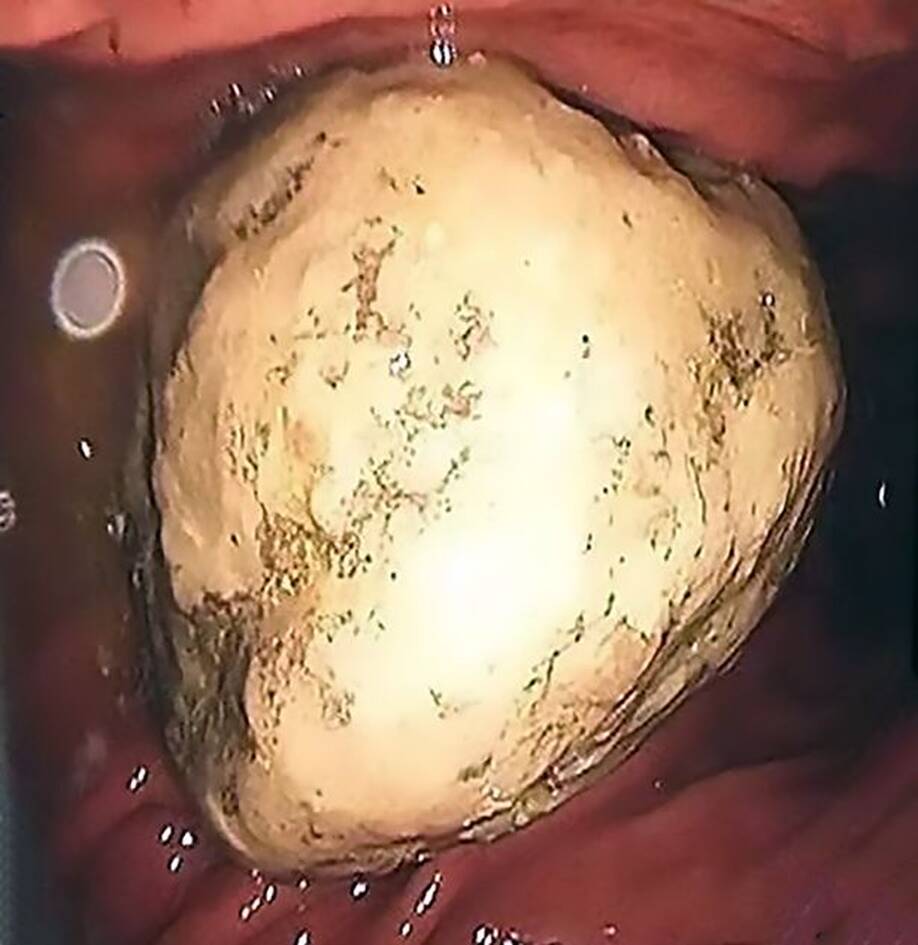

Απίστευτο και όμως αληθινό. Τεράστια πέτρα στη κοιλιά 40χρονης ασθενούς εξαιτίας της διατροφής της

Ούτε οι γιατροί που κλήθηκαν να χειρουργήσουν τη 40χρονη γυναίκα δεν μπορούσαν να πιστέψουν αυτό που επρόκειτο να αντιμετωπίσουν.

Η κυρία Zhang, παραπονιόταν διαρκώς για πόνους στην κοιλιά της. Οι συγγενείς της την πήγαν στο νοσοκομείο της πόλης Jiangsu με τους γιατρούς να μην μπορούν να εντοπίσουν τι ακριβώς συνέβαινε.

Έτσι αποφασίστηκε να μπει στο χειρουργείο, ώστε να δουν οι γιατροί τι έχουν να αντιμετωπίσουν.

Όταν ξεκίνησαν το χειρουργείο έπαθαν σοκ με αυτό που αντίκρισαν…

Η γυναίκα παραπονιόταν για πόνους στην κοιλιά, ωστόσο οι γιατροί δεν μπορούσαν να εντοπίσουν το πρόβλημα.

Εν τέλει αναγκάστηκαν να αφαιρέσουν μια πέτρα 5 εκατοστών. Πώς σχηματίστηκε; Η γυναίκα τρεφόταν με καβούρια και φρούτα με αποτέλεσμα η πρωτεΐνη και οι τανίνες να δημιουργήσουν αυτήν την πέτρα!

Μπροστά σε ένα τεράστιο σοκ βρέθηκαν οι γιατροί μόλις άνοιξαν το στομάχι μιας 40χρονης. Έτσι αποφάσισαν να την βάλουν στο χειρουργείο και μόλις διαπίστωσαν το πρόβλημα έμειναν με το στόμα ανοιχτό.

Η γυναίκα ευτυχώς αναρρώνει από την επέμβαση ας ελπίσουμε το ίδιο για τους γιατρούς…